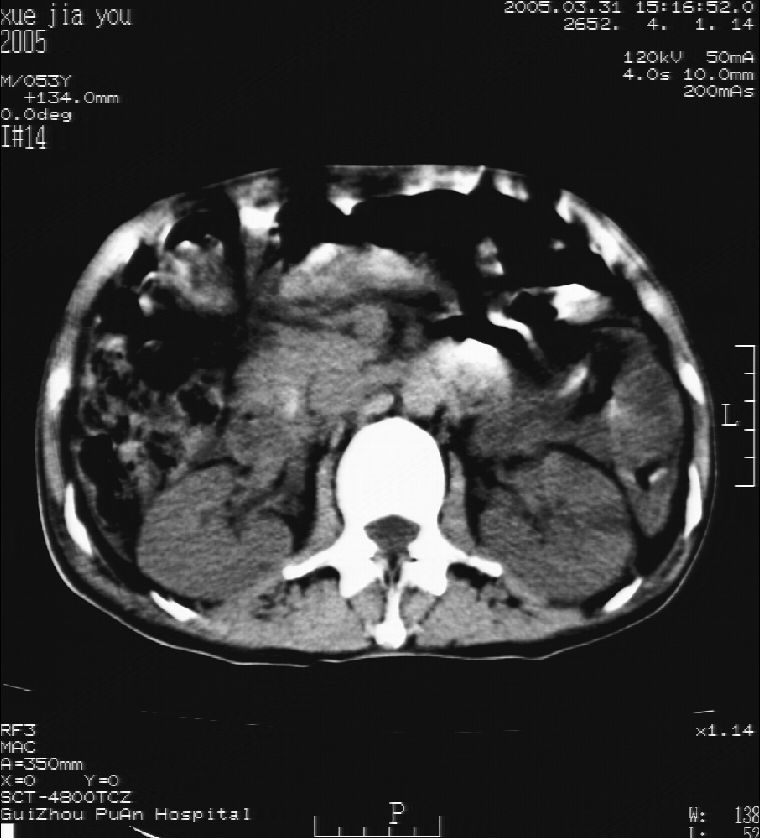

男 55岁  反复上腹痛1年,伴恶心呕吐。2005年做第一次检查后,到外院做b超检查提示肝囊肿,未做任何手术。2006年做过胆总管结石术。骨窗未见异常

这个病灶很有意思,怎么可能没有了呢?我考虑当时很可能是肝脏脓肿(b超示囊肿是有可能误诊的,因为影像表现都是低回声吗?),现在脓肿吸收了,肝脏萎缩,肝裂增宽了.别的肝叶代偿增大,不过现在左内叶的确有个占位,肝内多发结石,脾脏比以前大,不排除有肝硬化可能.建议增强扫描给于定性!!!!

肝硬化\\脾大,肝左叶肝癌可能性大,建议增强扫描.肝内胆管多发性结石.

1, 肝硬化,脾大;2,肝左叶肝癌可能性大,建议增强扫描.3,肝内胆管多发性结石.

考虑肝内胆管多发结石引起的肝内局部炎症,这样可以解释2005年肝右叶病灶的吸收和左叶新病灶.

肝硬化、脾大、肝内胆管多发结石。肝左叶低密度占位。建议增强扫描.排除肝癌